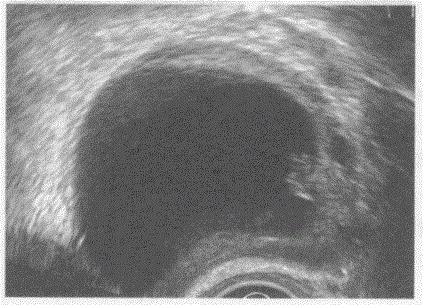

问题 临床资料:女,22岁,自述腹部进行性增大3月余。 临床物理检查:下腹部可扪及一肿物,质软。 超声综合描述:经阴道扫查左附件区可见5.5cm×3.6cm无回声区,囊壁不光滑,内可见乳头样中等回声突起,囊外壁不光滑,CDFI:囊壁及乳头内未见血流信号,囊壁外可见少许血流信号。见下图及彩图。 {图1} 超声提示:

选项 A.左卵巢癌 B.左卵巢畸胎瘤 C.左卵巢黄体囊肿 D.左卵巢囊肿(浆液性乳头状囊腺瘤)

答案 D